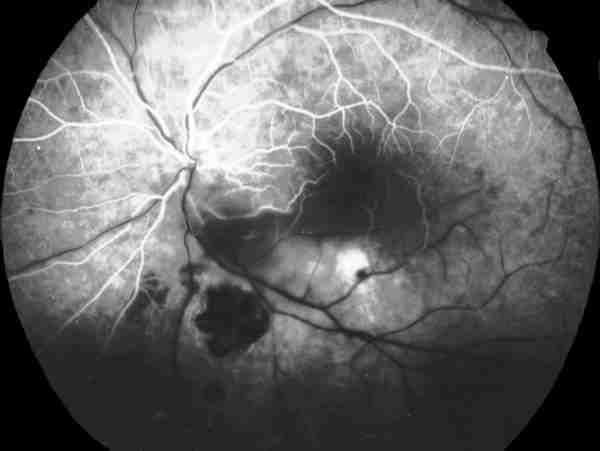

Figura 2

ANGIOGRAFÍA FLUORESCEÍNICA, FASE ARTERIOVENOSA PRECOZ. SE OBJETIVA UNA AUSENCIA DE LLENADO DE LA ARTERIA TEMPORAL INFERIOR A PARTIR DE UN FOCO DE HIPOFLUORESCENCIA QUE CORRESPONDE AL ÁREA DE RETINITIS.